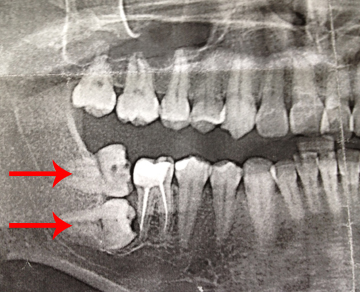

Дентальная галерея: ретинированный зуб клык и его лечение

Раздел: Компас решений